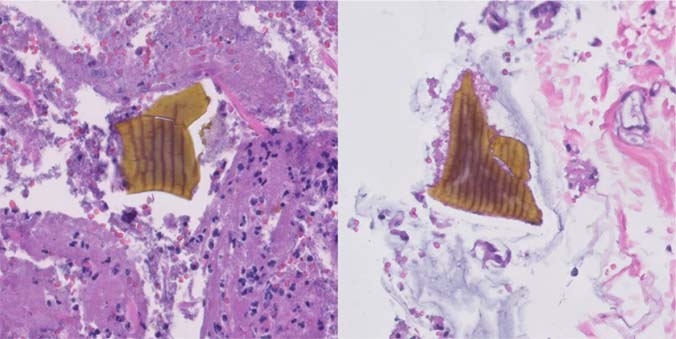

Figure 5: Medium power image of fibrinopurulent exudate, with sevelamer (left) and Kayexalate (right) crystals (Hematoxylin and eosin, 10× magnification).

Figure 6: High power images of fibrinopurulent exudate and embedded Kayexalate crystals with purple color and typical fish-scale pattern (Hematoxylin and eosin, 20× magnification).

Figure 7: High power images of fibrinopurulent exudate and embedded sevelamer crystals with yellow color and fish-scale pattern (Hematoxylin and eosin, 20× magnification).

Figure 8: High power image of Kayexalate (left) and sevelamer (right) crystals with differential staining patterns (Kinyoun, 20× magnification).